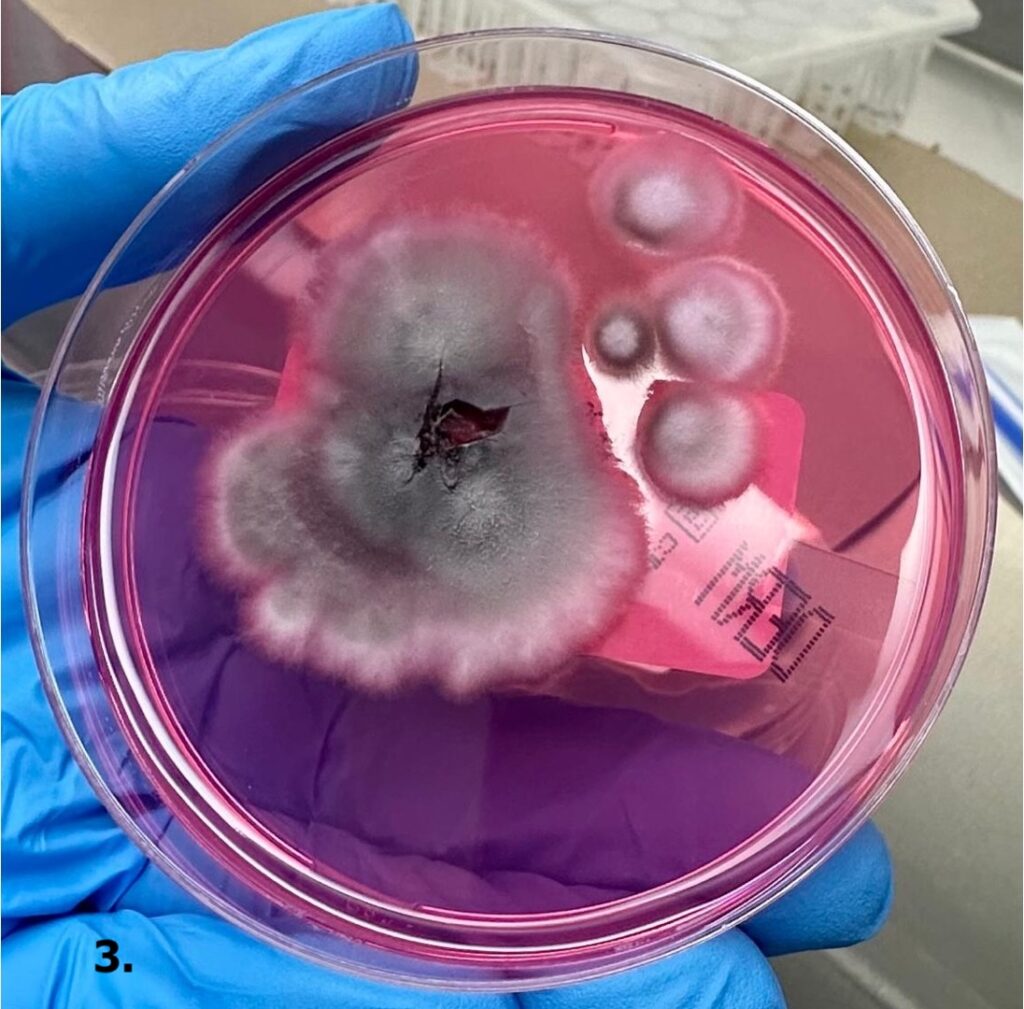

CASO CLÍNICO. Paciente pediátrico con esporotricosis de localización inusual

Cano Valencia AM y col.

La esporotricosis cutánea es una infección micótica causada por el complejo de hongos dimórficos Sporothrix schenckii. Clásicamente se ha descrito en hombres con ocupaciones relacionadas con la jardinería o la agricultura, sin embargo, se ha observado un aumento de su incidencia en niños, siendo la cara y las extremidades superiores los lugares más comúnmente afectados.

En este artículo, los autores presentan el caso clínico de una esporotricosis cutánea pediátrica con una localización atípica. Asimismo, describen algunos hallazgos dermatoscópicos y el uso de la crioterapia asociada al itraconazol con buenos resultados clínicos.

Cultivo en agar Sabouraud dextrosa con colonias glabras, húmedas, de color crema y con crecimiento radial